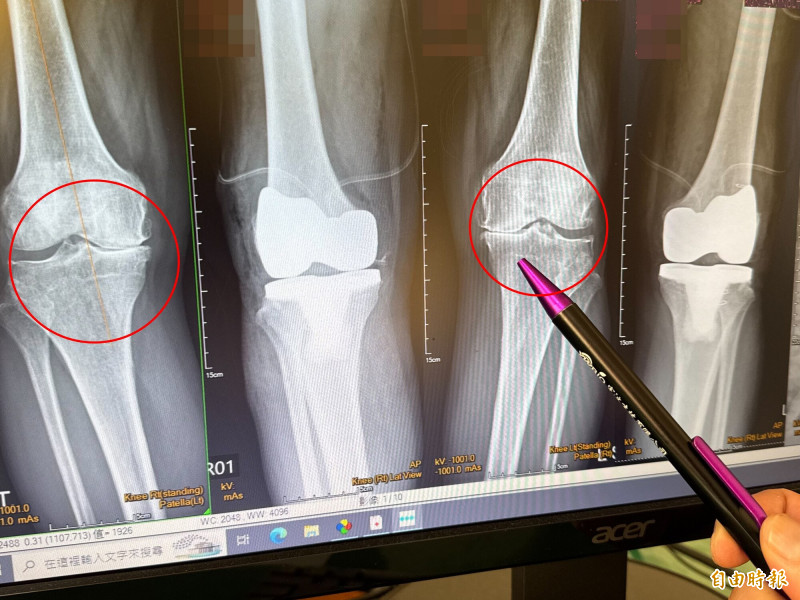

大甲李綜合醫院副院長、骨科主治醫師王芳英表示,婦人是第四期的退化性關節炎,雙腳內翻變成10度,外觀看起來呈現O型腿,腳無法伸直,另外脊椎第2到第5節滑脫長骨刺,背部往前傾。門診時,非常困擾,詢問「到底要先治療雙膝還是脊椎」,他分析後建議先置換人工膝關節。

王芳英說,婦人雙膝變形嚴重無法站直,如果沒有先開刀治療,背部會持續往前傾,同時建議一次進行雙腳的膝關節置換,避免完成單腳人工膝關節置換後造成長短腳,在身體重心不穩走路下,讓脊椎滑脫的症狀更加嚴重,婦人在置換雙膝後,隔天便能下床正常走路。